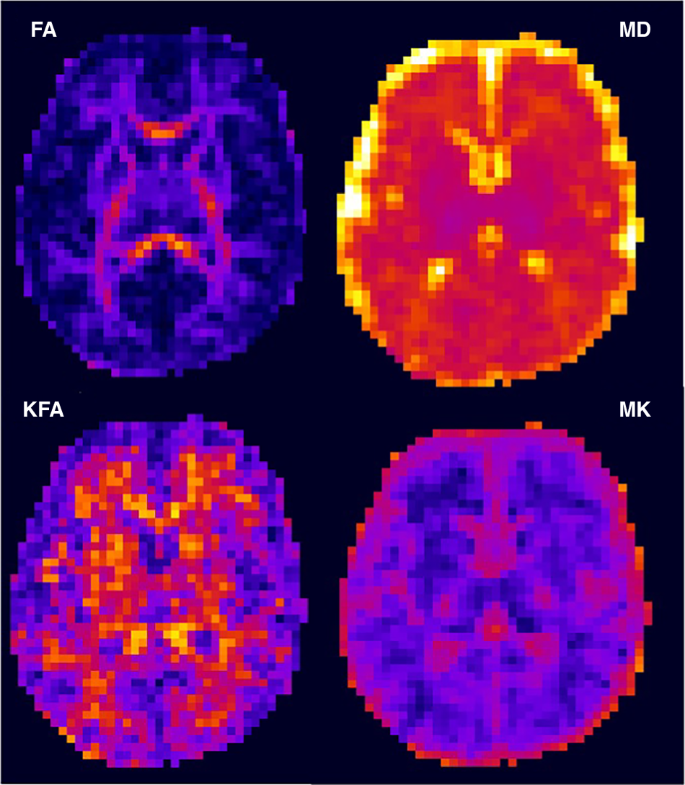

DKI data were quality controlled by removing image volumes and associated gradient directions containing excessive head motion or signal drop-out artifacts. Cleaned DKI data were processed using PyDesigner42 resulting in rotationally invariant parametric maps derived from the estimated diffusion and kurtosis tensors. Diffusion parameters calculated and used in our analysis included MD, FA, MK and KFA. Representative parametric maps in a single neonate are shown to highlight the differences in diffusivity and kurtosis metrics in Fig. 2. Example images of neonatal brain infarcts as viewed with both diffusivity and kurtosis are provided in Fig. 3.

Top row, conventional diffusivity measures of fractional anisotropy (FA) and mean diffusivity (MD). Bottom row, kurtosis fractional anisotropy (KFA) and mean kurtosis (MK). The diffusivity has units of μm2/ms. While the FA is quite low in most regions (deep purple) except the genu and the splenium of the corpus callosum, the KFA shows higher values (red/yellow) with more diversity in the reported higher-order anisotropy, reflecting tissue complexity. Within the MD map that the thalami (purple voxels) are approaching their asymptotic lowest value, while the MK map shows greater detail in this region. Interestingly, the MK has low values within the WM, with slightly higher values in the cortex and thalamic gray matter. Eventually, during myelination and maturation, the MK in the WM will exceed that in the gray matter due to the restriction from biological barriers, such as myelin.